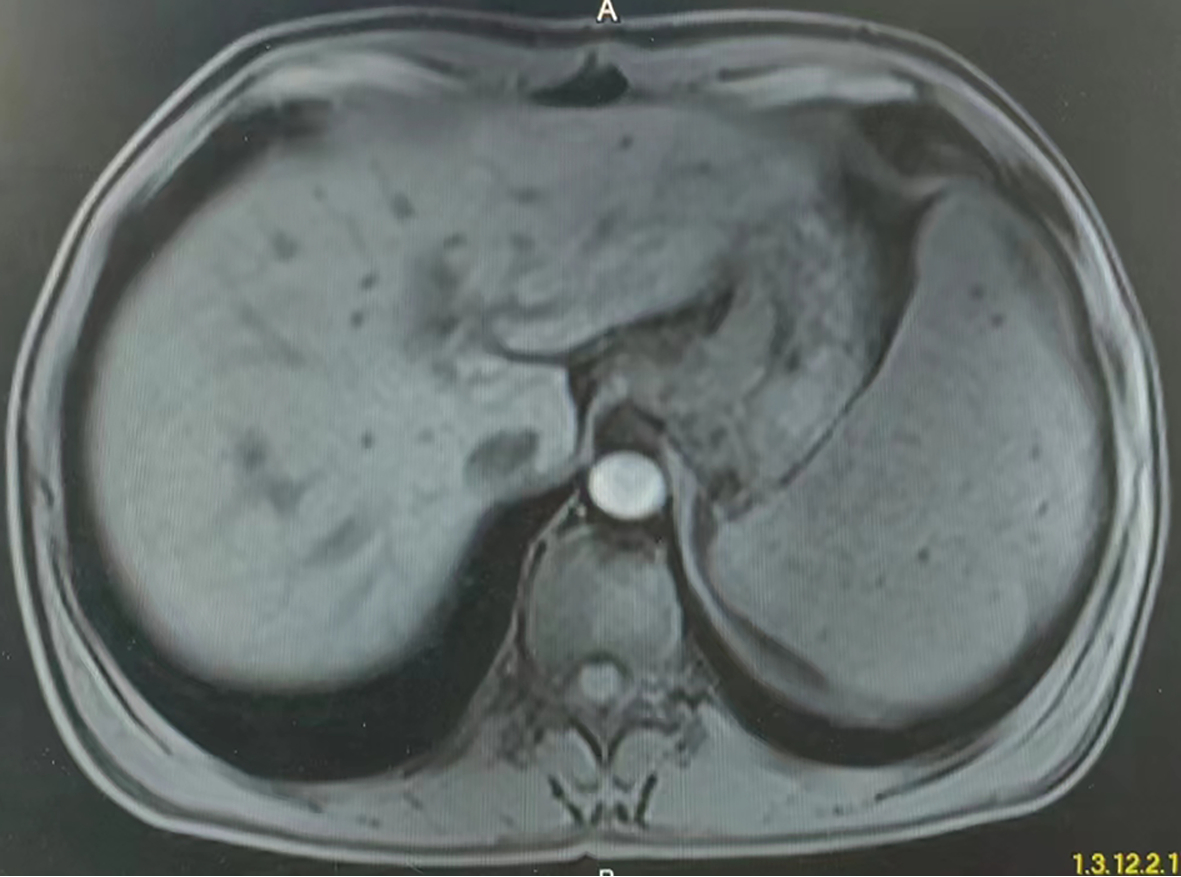

Research advances in congenital extrahepatic portosystemic shunt

Abstract(1666) HTML (1247) PDF (2399KB)(127)

Abstract:

Congenital extrahepatic portosystemic shunt (CEPS) is also called Abernethy malformation, with the manifestation of congenital abnormal anastomosis between the portal vein and the inferior vena cava. CEPS is extremely rare in clinical practice and has diverse clinical symptoms, which often leads to missed diagnosis and misdiagnosis. This article reviews the pathogenesis, classification, clinical manifestation, diagnosis, and treatment of CEPS, so as to improve the awareness of this disease and provide a reference for further standardization of its diagnosis and treatment process in the future.